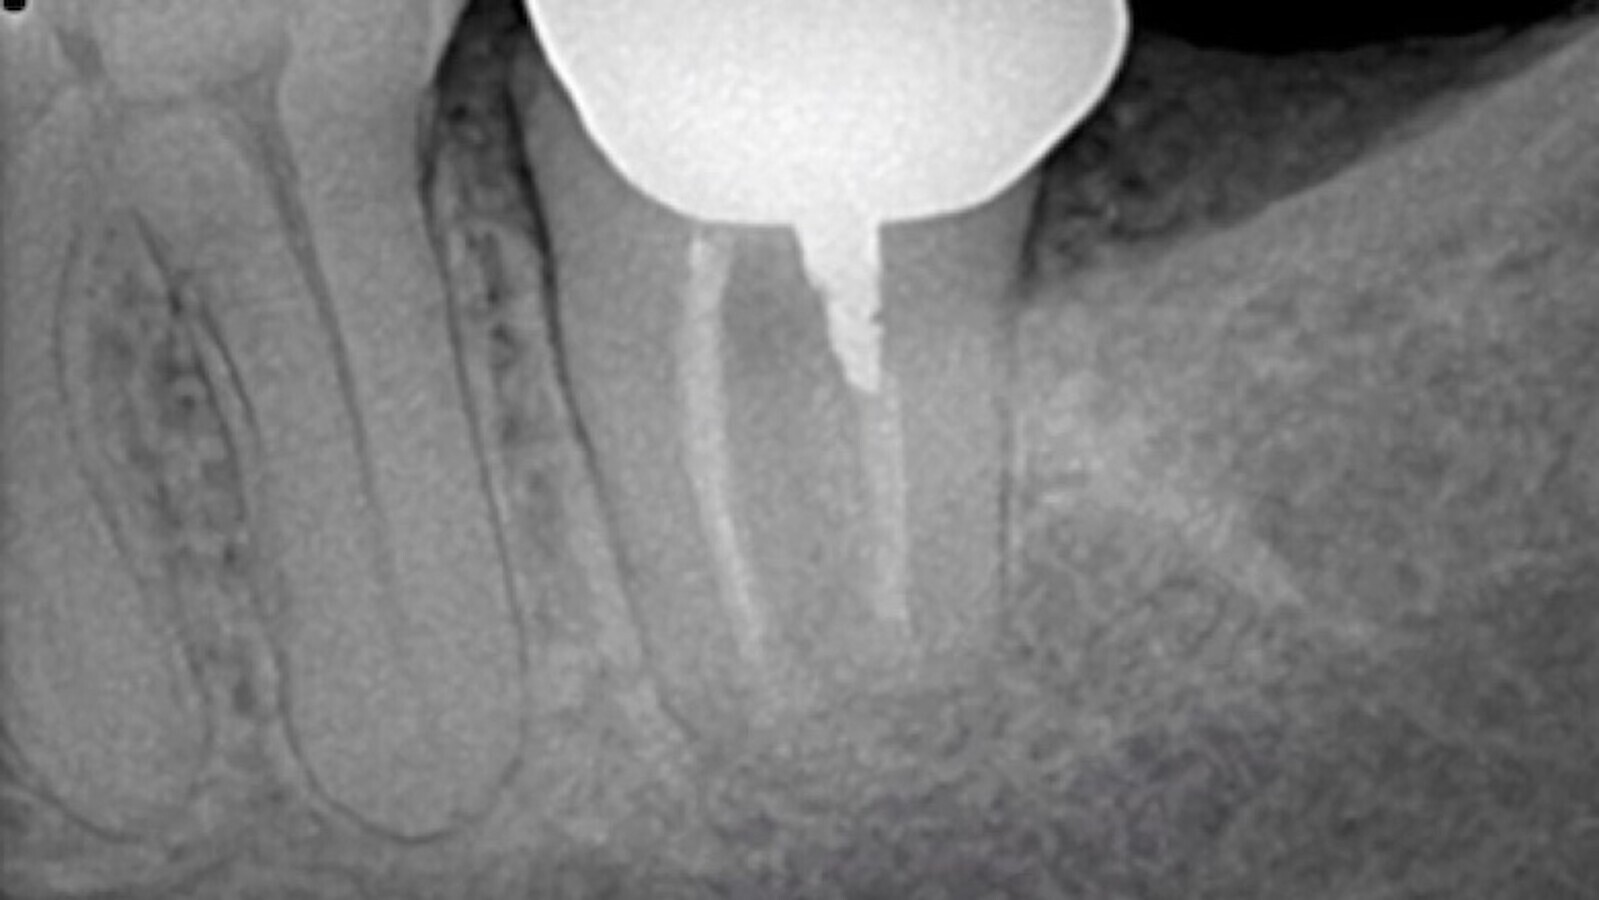

Figura 4. Control 1 mes después del reimplante intencional del diente 37.